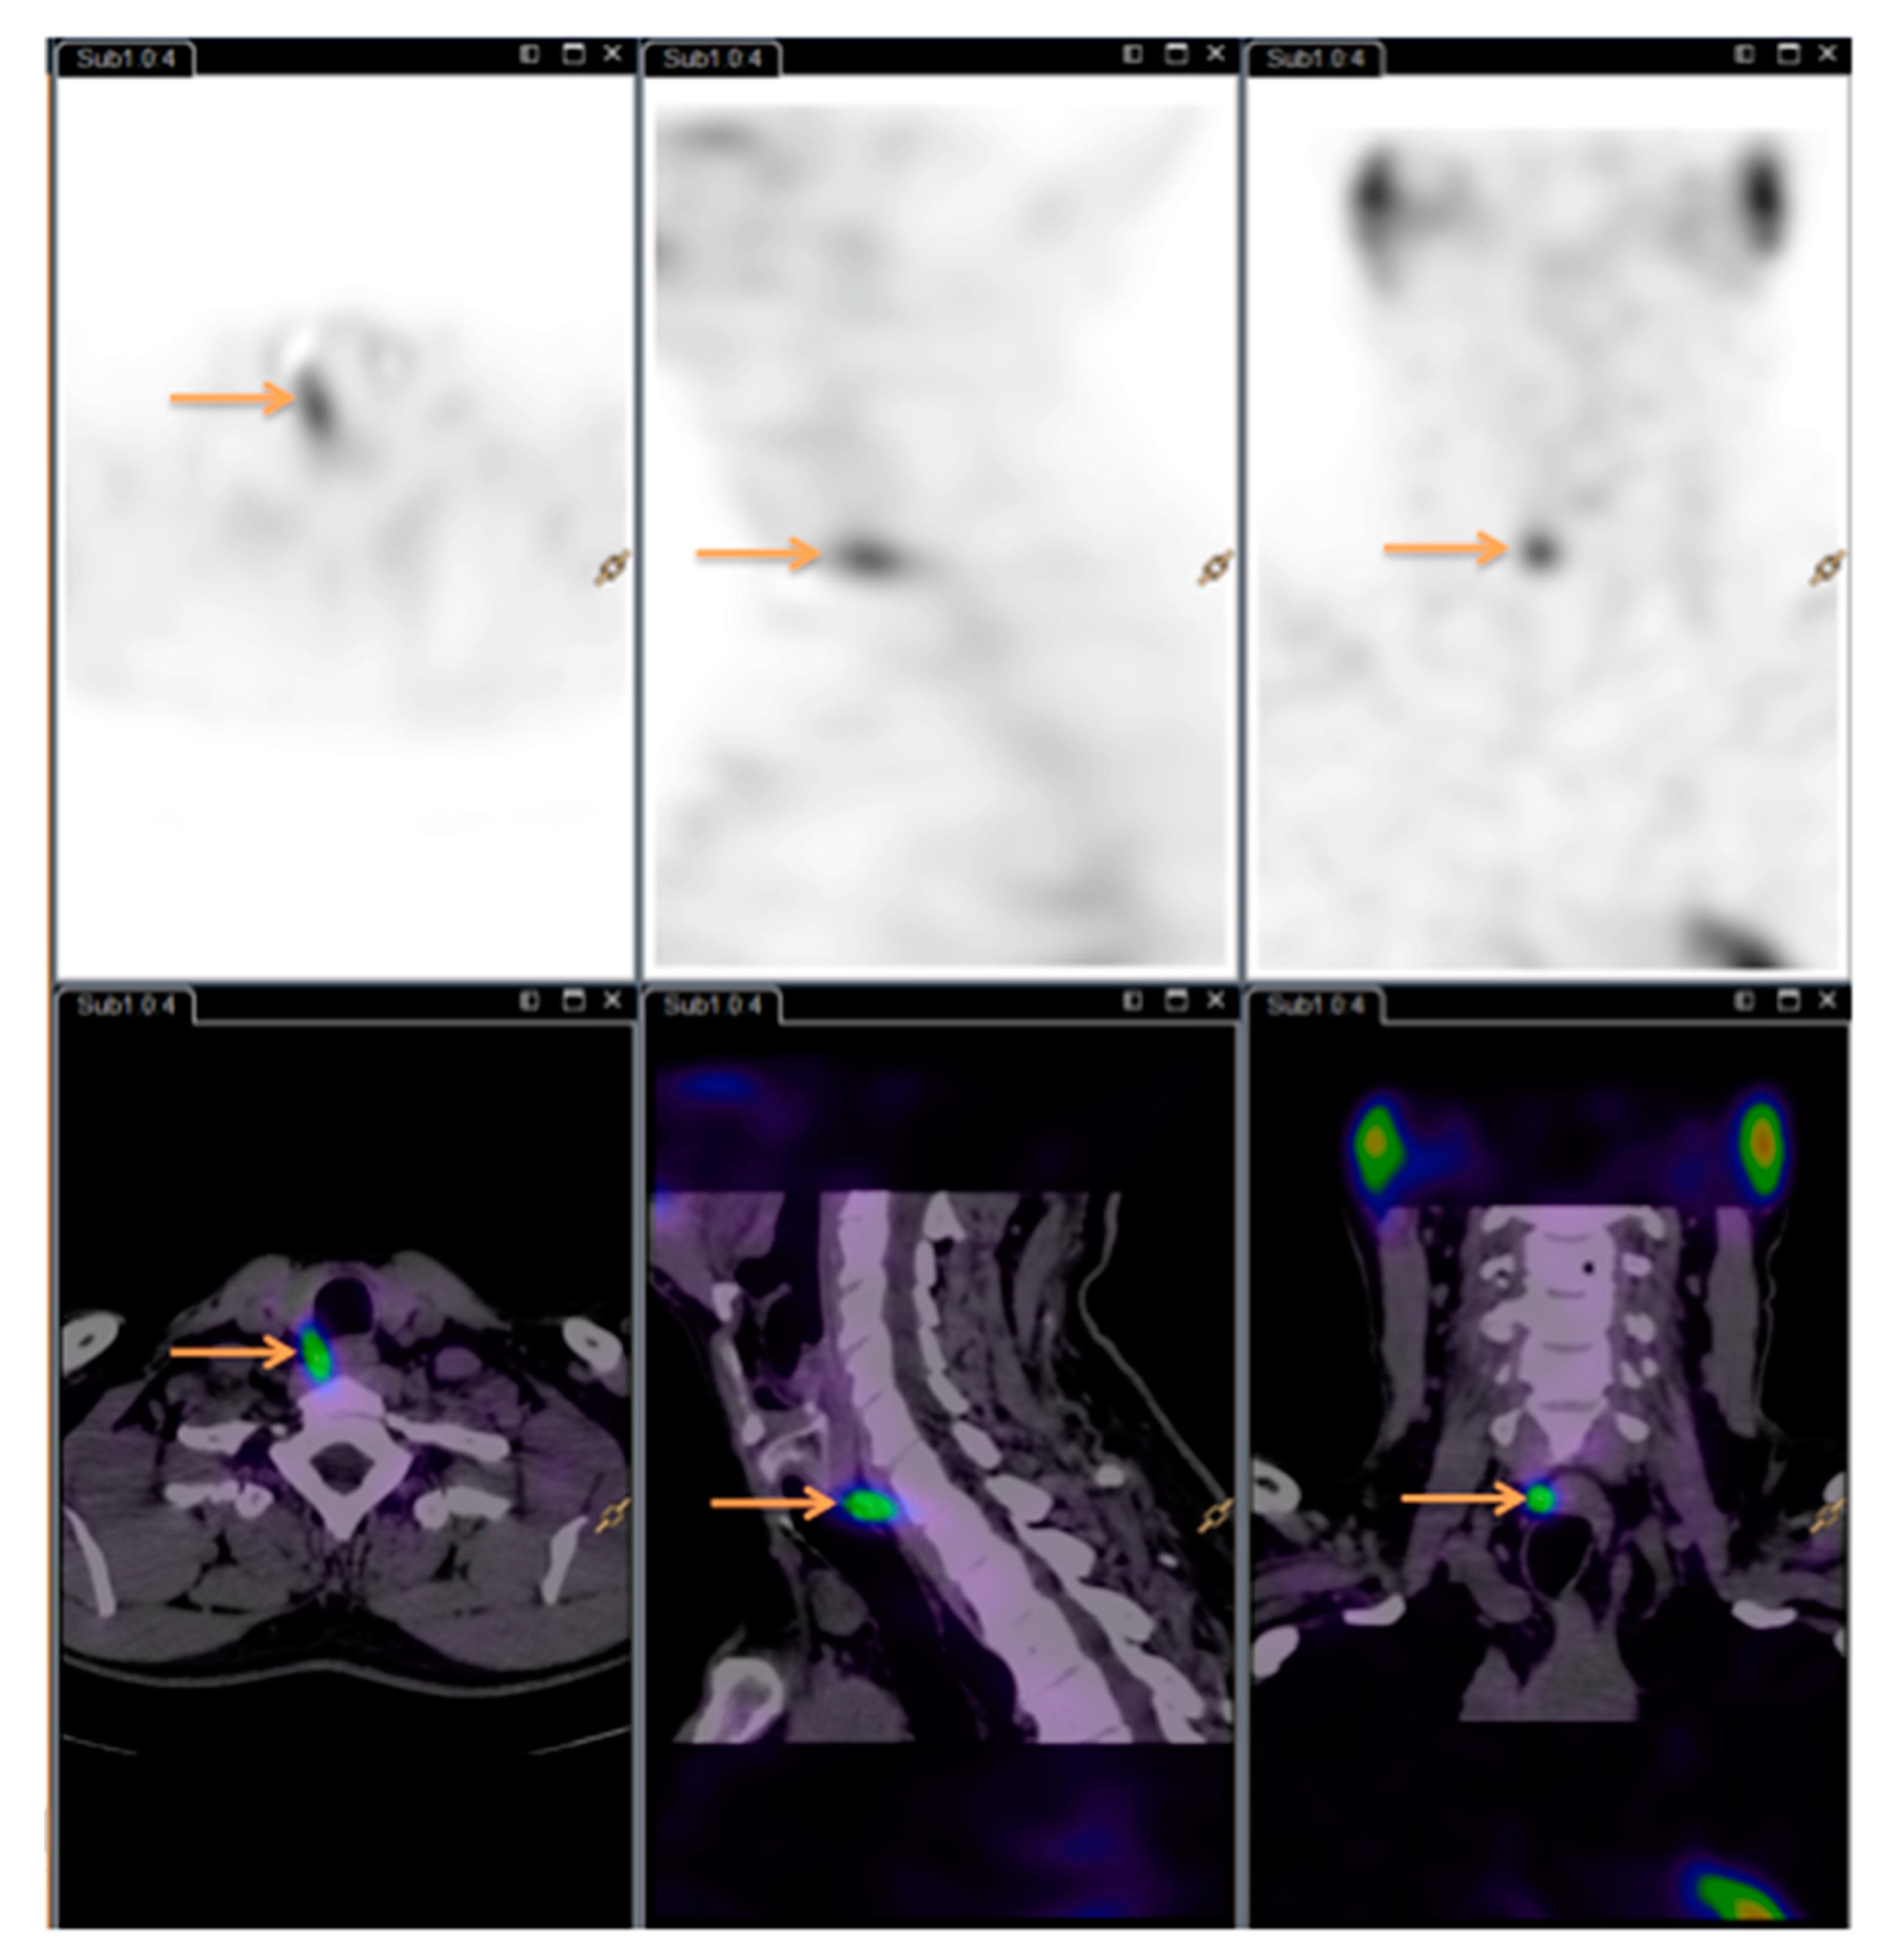

See Figure 1 and Figure 2 for images (same patient as Figure 3).

Figure 2. Dual isotope subtraction single-photon emission computed tomography/computed tomography (SPECT/CT) image. Arrows showing the hyperfunctioning parathyroid gland.